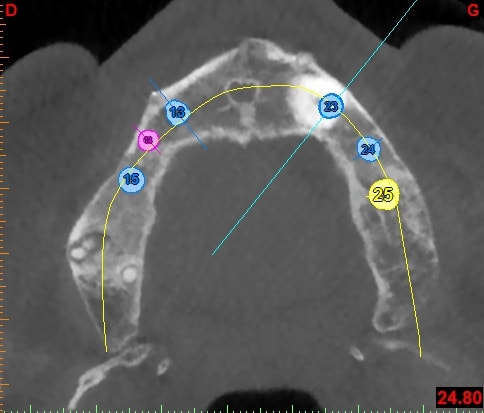

patiente de 80ans, canine incluse depuis donc pas mal de temps. ATCD de prothese amovible depuis 15ans. Je crains que sa canine soir hyper ankylosé et je me propose donc d'implanter au travers.

Canine coupe vestibulo linguale b2loil - Eugenol

C'est bien ma crainte mais j'ai plusieurs questions : les forets antogyr ne risquent-ils pas de déraper au contact de la racine de 13 ?

Y a-t-il bien une sidération nerveuse de 13 qui m'évite tout tt endo de 13 (impossible en laissant 13 en place d'ailleurs)?